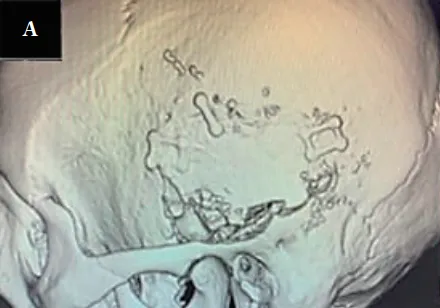

手术操作细节

手术采用U形皮肤切口,环绕耳廓获取大面积带蒂筋膜骨膜瓣,为后续修复做准备。从中颅底分离颞叶硬脑膜过程中,精确识别并电凝、离断脑膜中动脉。

随后从小脑幕方向切开颅中窝硬脑膜,夹闭上岩窦近远端,创建安全操作空间。显微镜下清晰辨识肿瘤前方面神经,在保护颈静脉球和面神经前提下,逐步完整切除肿瘤。